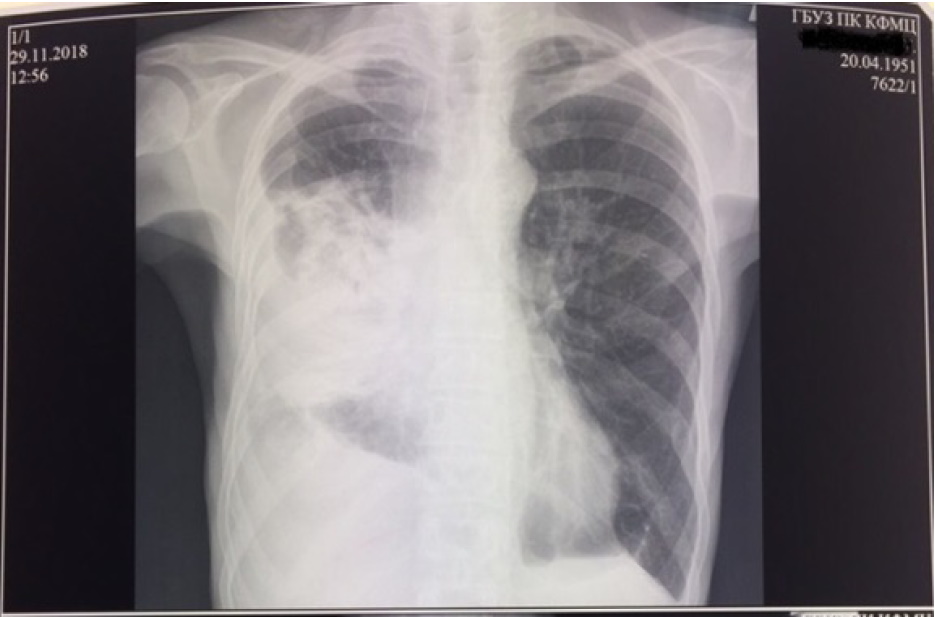

Рентгенография от 29.11.2018: в S1-2 левого легкого сохраняется небольшой фокус инфильтрации, связанный с междолевой плеврой. В средних и нижних отделах правого легкого определяется обширная интенсивная инфильтрация, связанная с корнем и утолщенной плеврой. В правой плевральной полости определяется жидкость над диафрагмой. В левой плевральной полости жидкости нет. Средостение не смещено (рис. 8).

Рис. 8. Рентгенограмма органов грудной клетки от 29.11.2018